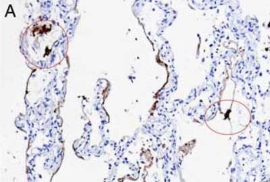

检测SARS-CoV-2 RNA。A和B分别为使用竞品和Enzo探针在COVID-19肺炎样品中进行SARS-CoV-2 RNA原位杂交。竞品探针还会标记巨噬细胞(图A中圆圈部分)。

Nuovo GJ et Al. Appl Immunohistochem Mol Morphol. 2022 Feb 1;30(2):83-90.

使用 Enzo's AMPIVIEW™ RNA 探针时,SARS-CoV-2 阴性组织无背景染色

"使用其他品牌探针和Enzo AMPIVIEW™ 探针通过ISH检测了一些正常的大脑和胎盘作为SARS-CoV-2 RNA的阴性对照。对比竞品探针的背景(红细胞),使用Enzo探针的背景低。" ——Dr. Nuovo, 俄亥俄州立大学 |